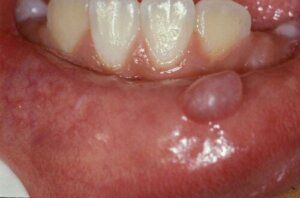

Det er godartede cystiske læsioner, der er dannet af en forstyrrelse i de mindre spytkirtler. De indeholder normalt slim og er beklædt med slimhindeceller. De kan være overfladiske eller dybe og varierer i størrelse fra et par millimeter til 3 centimeter.

Slimhindecysten viser sig pludselig som en lille blære eller knude fyldt med slim inde i munden, som regel på underlæben. Den kan være gennemsigtig blå i farven eller bevare samme farve som den underliggende slimhinde. De er smertefri, medmindre de ledsages af et sår.

Nogle mennesker forveksler dem ofte med mundsår. Sidstnævnte er imidlertid ulcerøse læsioner med rødlige kanter og hvide centre, der giver smerte og ubehag. Selv om underlæben er det hyppigste sted, kan de også dannes på tungen, ganen, slimhinden på kinden og på mundbunden.